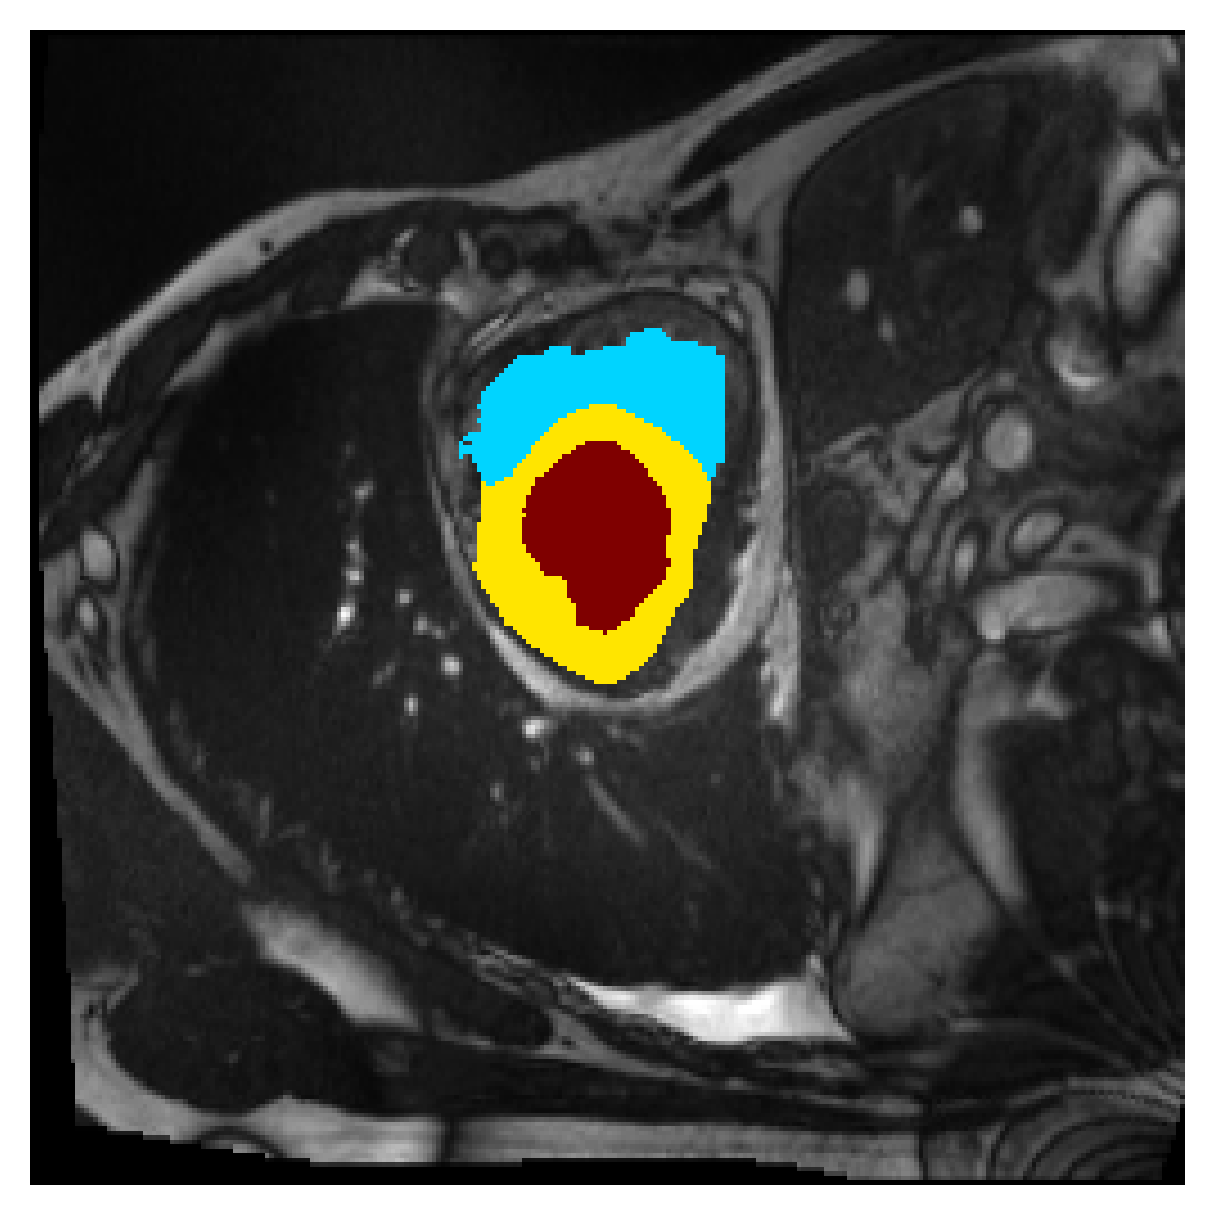

Qualitative comparison

| (a) Ground truth | (b) , full | (c) , weak | (d) |

| (full) | supervision | supervision | |

|

|

|

|

|

|

|

|

|

|

|

|

| (e) | (f) | (g) | (h) CRF-loss |

In Figure 6 we provide qualitative results on a number of randomly chosen test set slices. Upon visual inspection, we can observe that training with the intensity-aware distances (particularly with and ) follows the image gradients better and is better at recovering the underlying shape than the Euclidean version. The CRF-loss seems to recover the shape of the myocardium and left ventricle to some extent, but fails entirely on the right ventricle.